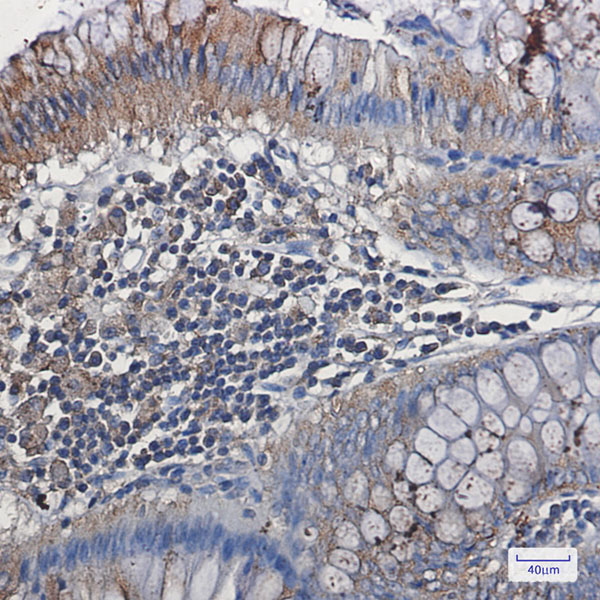

The VEGF vegfa (Catalog #AAA297045) is a Recombinant Antibody produced from CHO Cell and is intended for research purposes only. The product is available for immediate purchase. The Anti-VEGF Reference Antibody (BioMab patent anti-VEGF) reacts with Human, Rabbit and may cross-react with other species as described in the data sheet. AAA Biotech's VEGF can be used in a range of immunoassay formats including, but not limited to, FA (Functional Assay), FCM/FACS (Flow Cytometry), ELISA. Researchers should empirically determine the suitability of the VEGF vegfa for an application not listed in the data sheet. Researchers commonly develop new applications and it is an integral, important part of the investigative research process. It is sometimes possible for the material contained within the vial of "VEGF, Monoclonal Recombinant Antibody" to become dispersed throughout the inside of the vial, particularly around the seal of said vial, during shipment and storage. We always suggest centrifuging these vials to consolidate all of the liquid away from the lid and to the bottom of the vial prior to opening. Please be advised that certain products may require dry ice for shipping and that, if this is the case, an additional dry ice fee may also be required.Precautions